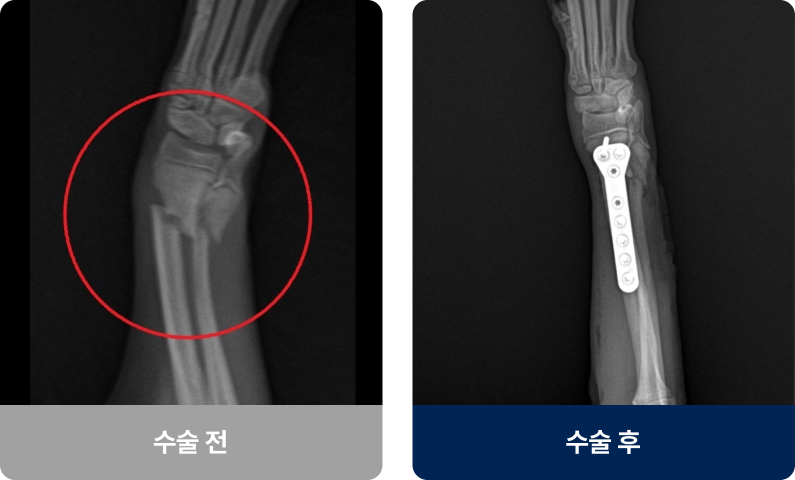

뼈의 연속성이 끊어진 상태로, 충격(낙상·교통사고)이나 병적 요인으로 발생합니다. 갑자기 다리를 절고 신음소리를 내거나 움직이지 않고 일어서거나 걷지 못하는 증상을 보입니다. 대부분 수술이나 깁스 고정을 통해 치료 후, 일정 기간의 휴식과 재활치료를 통해 근력과 관절 운동을 회복해야 합니다.

외과적 치료법(수술적 치료)

수술법은 골절 부위·형태·체중에 따라 달라지지만, 현재 플레이트 고정술이 가장 널리 사용되고 있습니다.

수술법은 골절 부위·형태·체중에 따라 달라지지만,

현재 플레이트 고정술이 가장 널리 사용되고 있습니다.